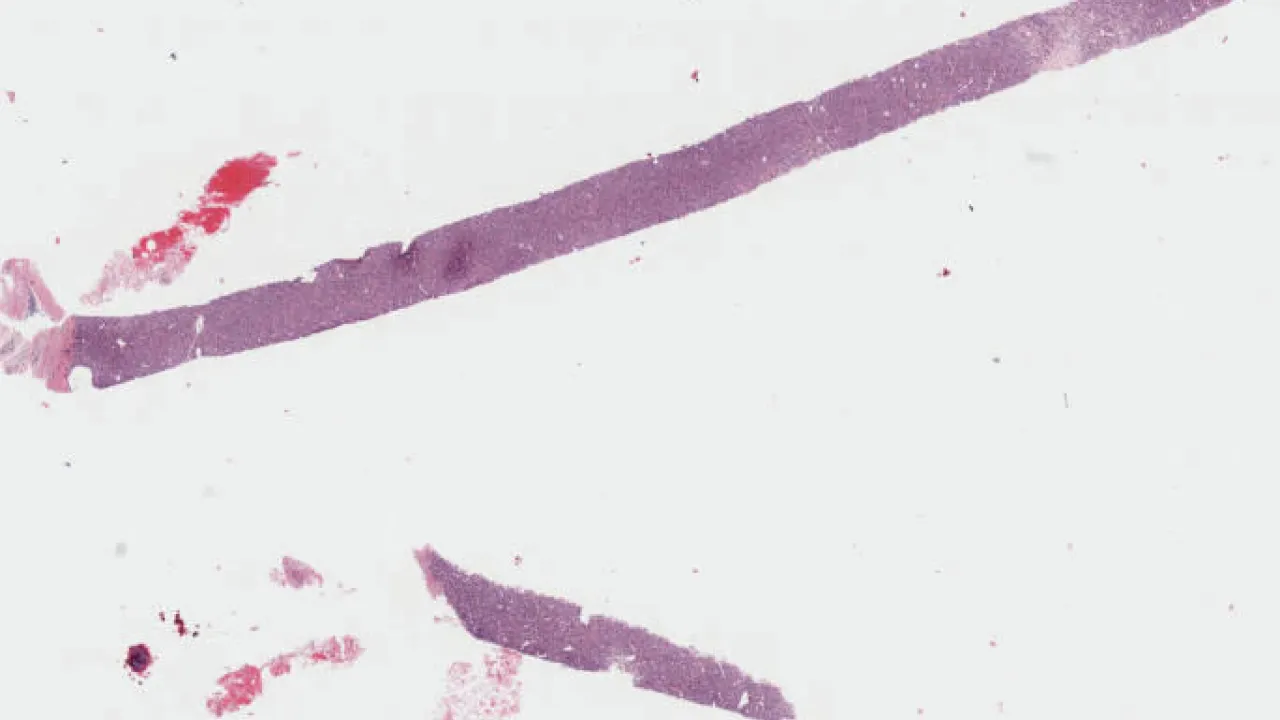

Small Intestine, Peutz-Jeghers polyp